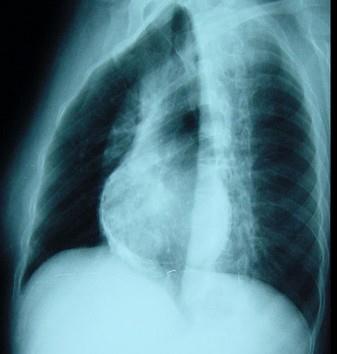

女性,46岁。间断胸痛4年,胸闷2年,外院诊断为“风湿性心脏病”。入院查体:血压110/65mmHg,颈静脉无充盈,心律75次/分,未闻及杂音,双下肢浮肿...

问题 女性,46岁。间断胸痛4年,胸闷2年,外院诊断为“风湿性心脏病”。入院查体:血压110/65mmHg,颈静脉无充盈,心律75次/分,未闻及杂音,双下肢浮肿,肝脏肋下2cm。 诊断明确后应尽早手术,围术期要点为 ( )